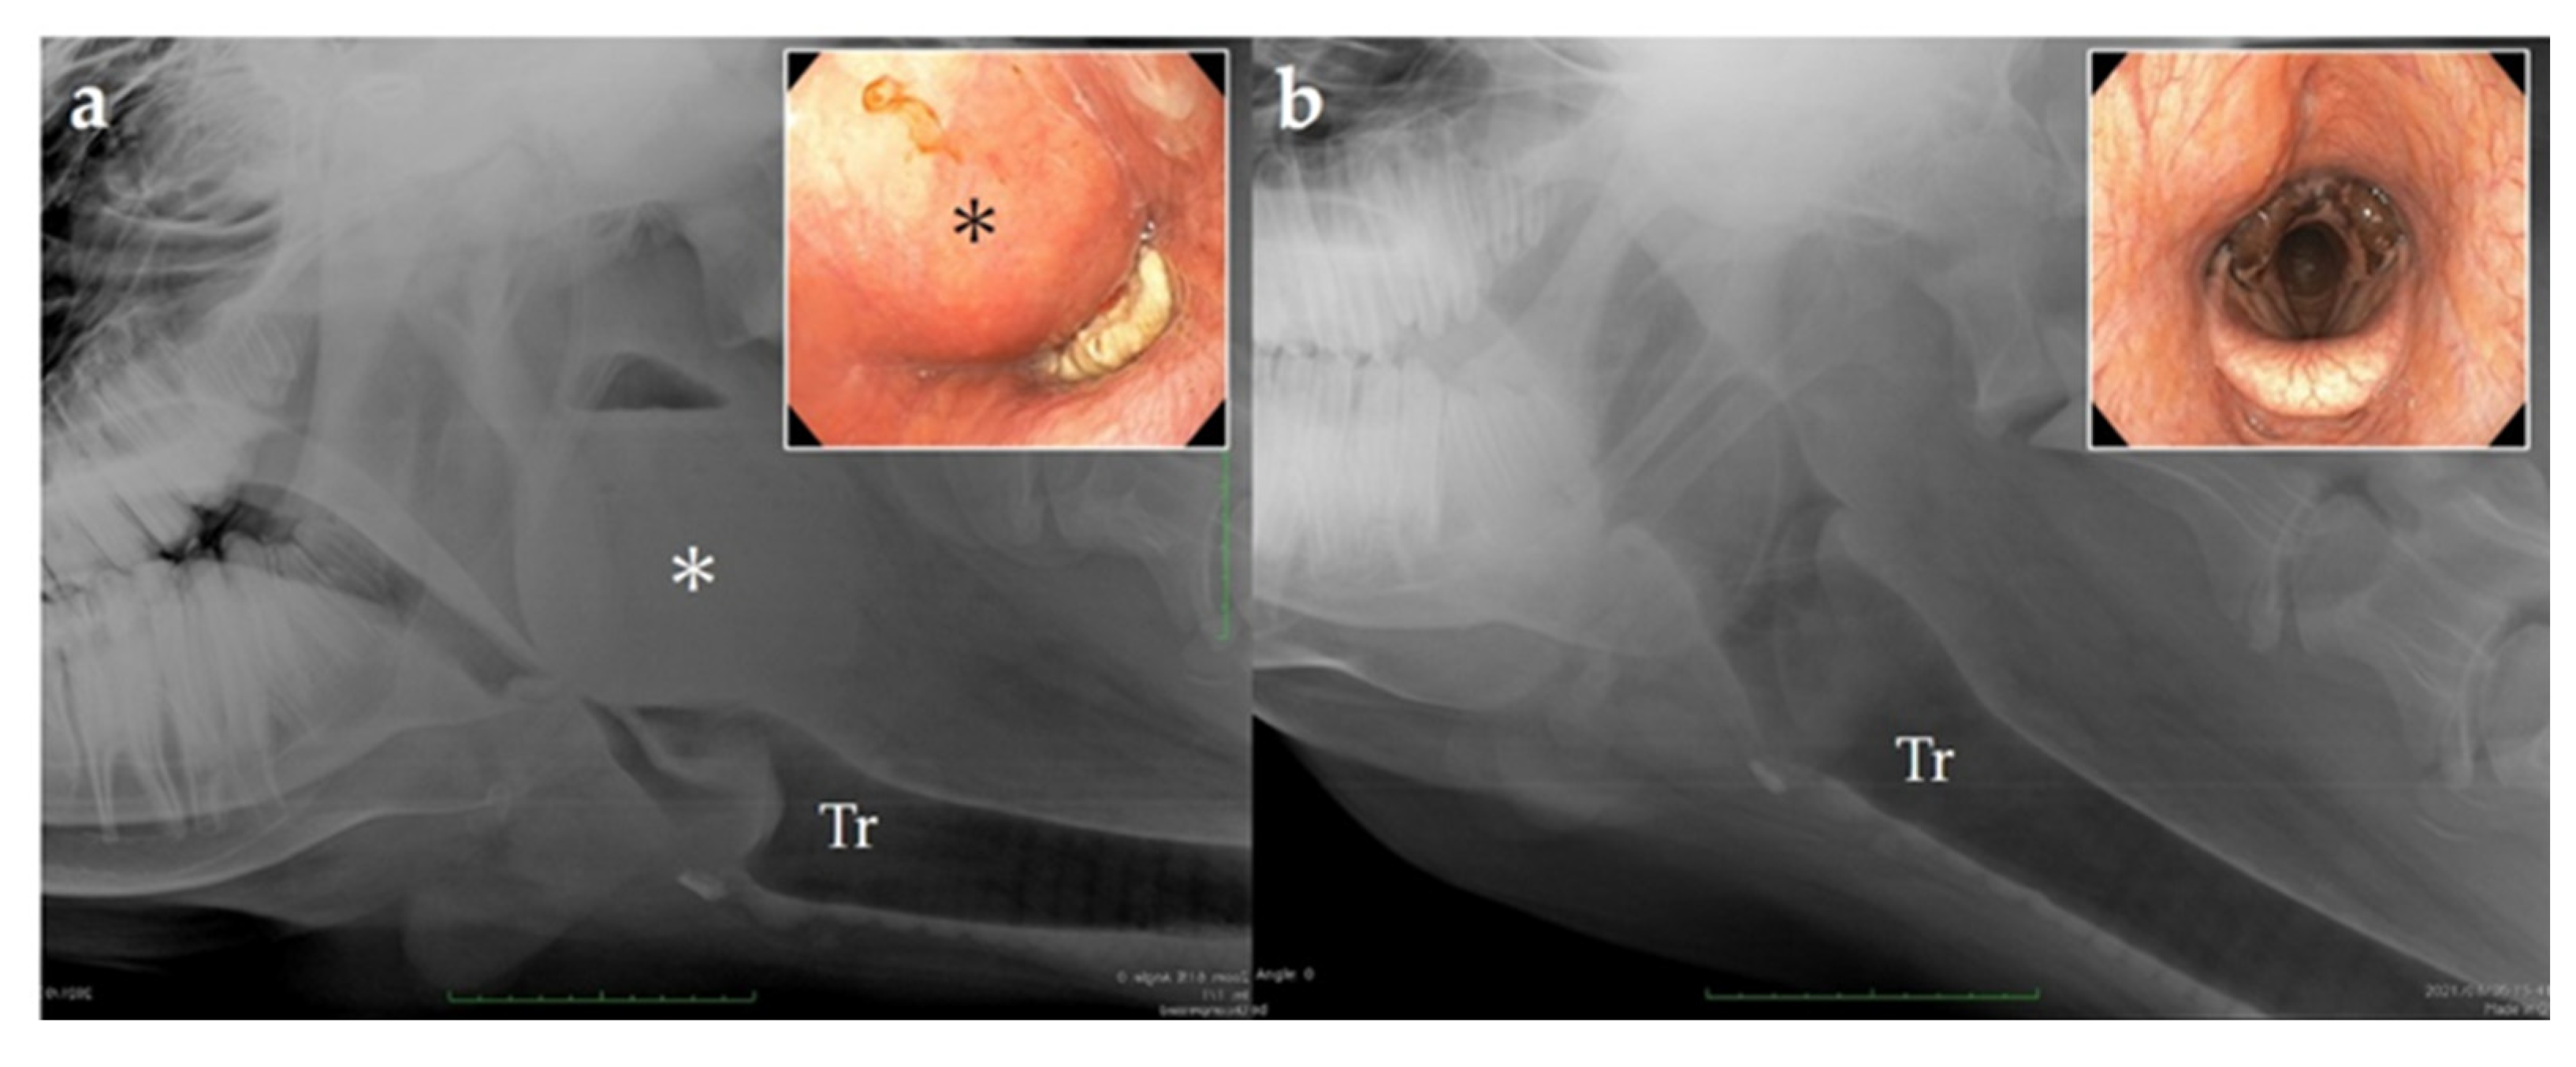

Following curettage, the abscess cavity was washed with 2% povidone–iodine (Figure 4). The cow’s head was lowered intraoperatively to facilitate the drainage.

Recovery from anesthesia postoperatively was uneventful. Wheezing disappeared immediately after the surgery, and appetite was restored the following day. Follow-up endoscopies were performed through the nasal cavity, and the abscess cavity was washed with saline and 2% povidone–iodine for 3 days (Figure 5). Cefazolin sodium was also administered intravenously for 3 days postoperatively.

5. Outcome and Follow-Up

The patient was discharged on postoperative day 4. Endoscopy 16 days postoperatively showed that the dorsal pharyngeal swelling had disappeared, and the airway patency had improved significantly (Figure 6). The owner reported that the cow had an uneventful recovery and was healthy even 1 year postoperatively.

Figure 4. Endoscopic view of the pharyngeal abscess cavity (a) before and (b) after manual drainage and lavage.

Figure 6. Lateral radiography of the pharyngeal area and endoscopic view via the nasal cavity. (a) Day of admission; (b) sixteen days after the surgery. Tr: trachea; *: abscess.